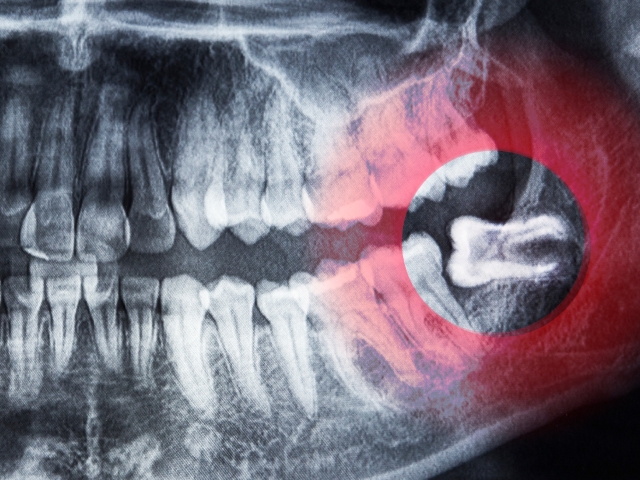

特に注意が必要なのは「下顎の埋伏智歯」です。

下顎の骨は硬く、親知らずの近くには「下歯槽神経」という太い神経が通っています。神経に近い場合は、CT撮影を行い、安全性を十分に確認した上で慎重に抜歯を行う必要があります。